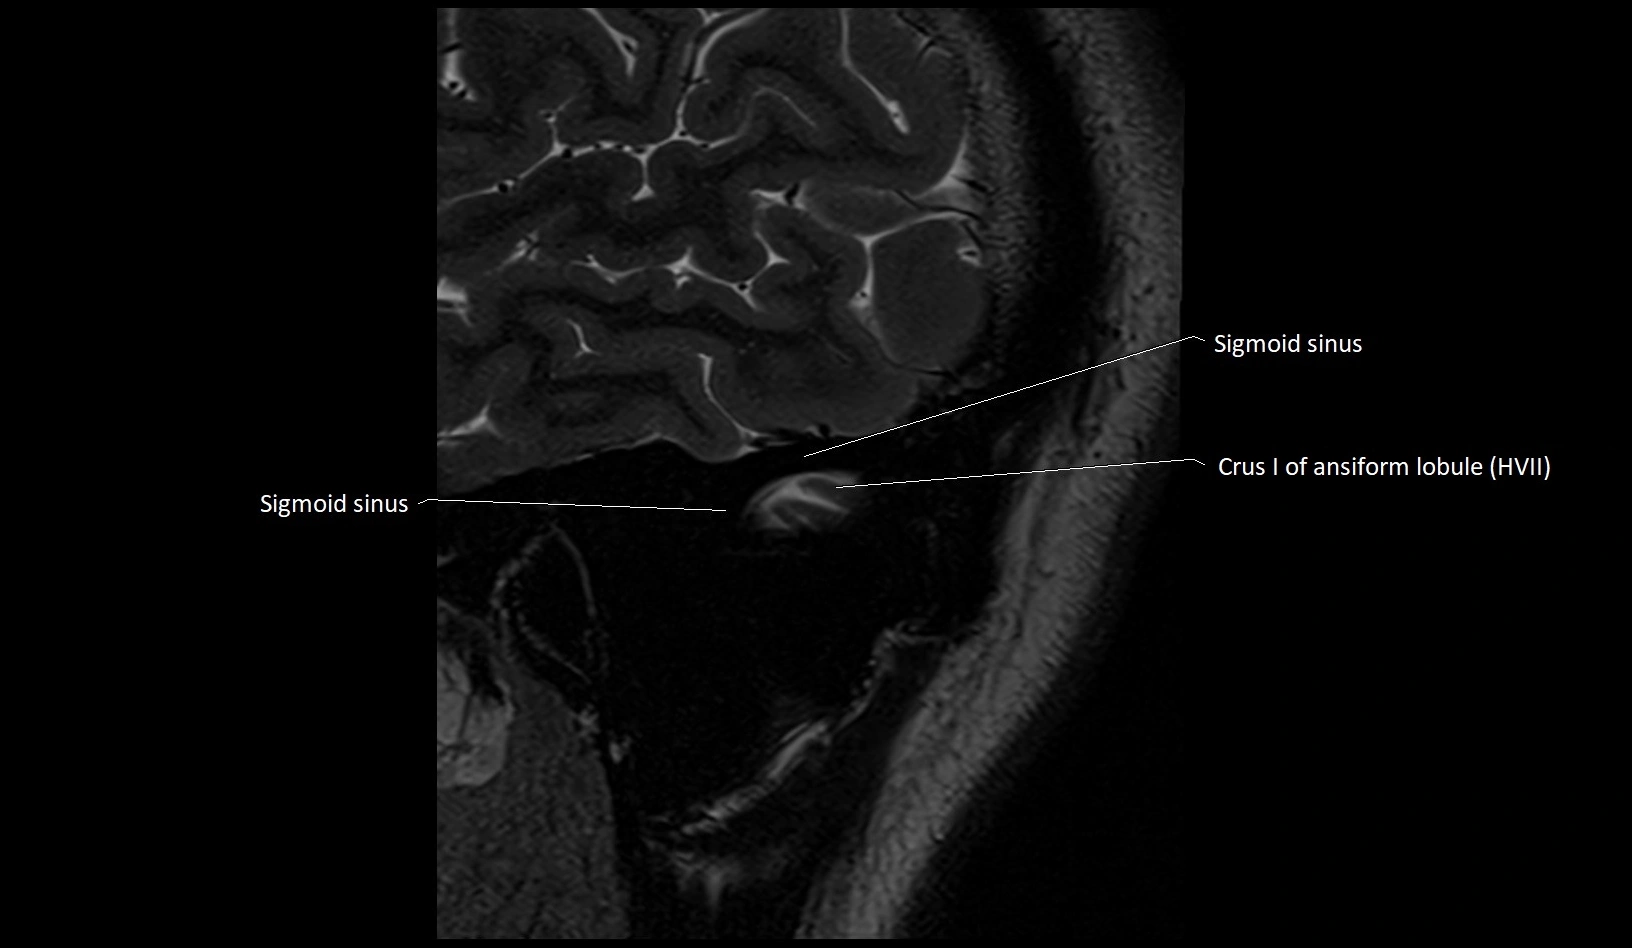

- Crus I of ansiform lobule of cerebellum

- Sigmoid sinus